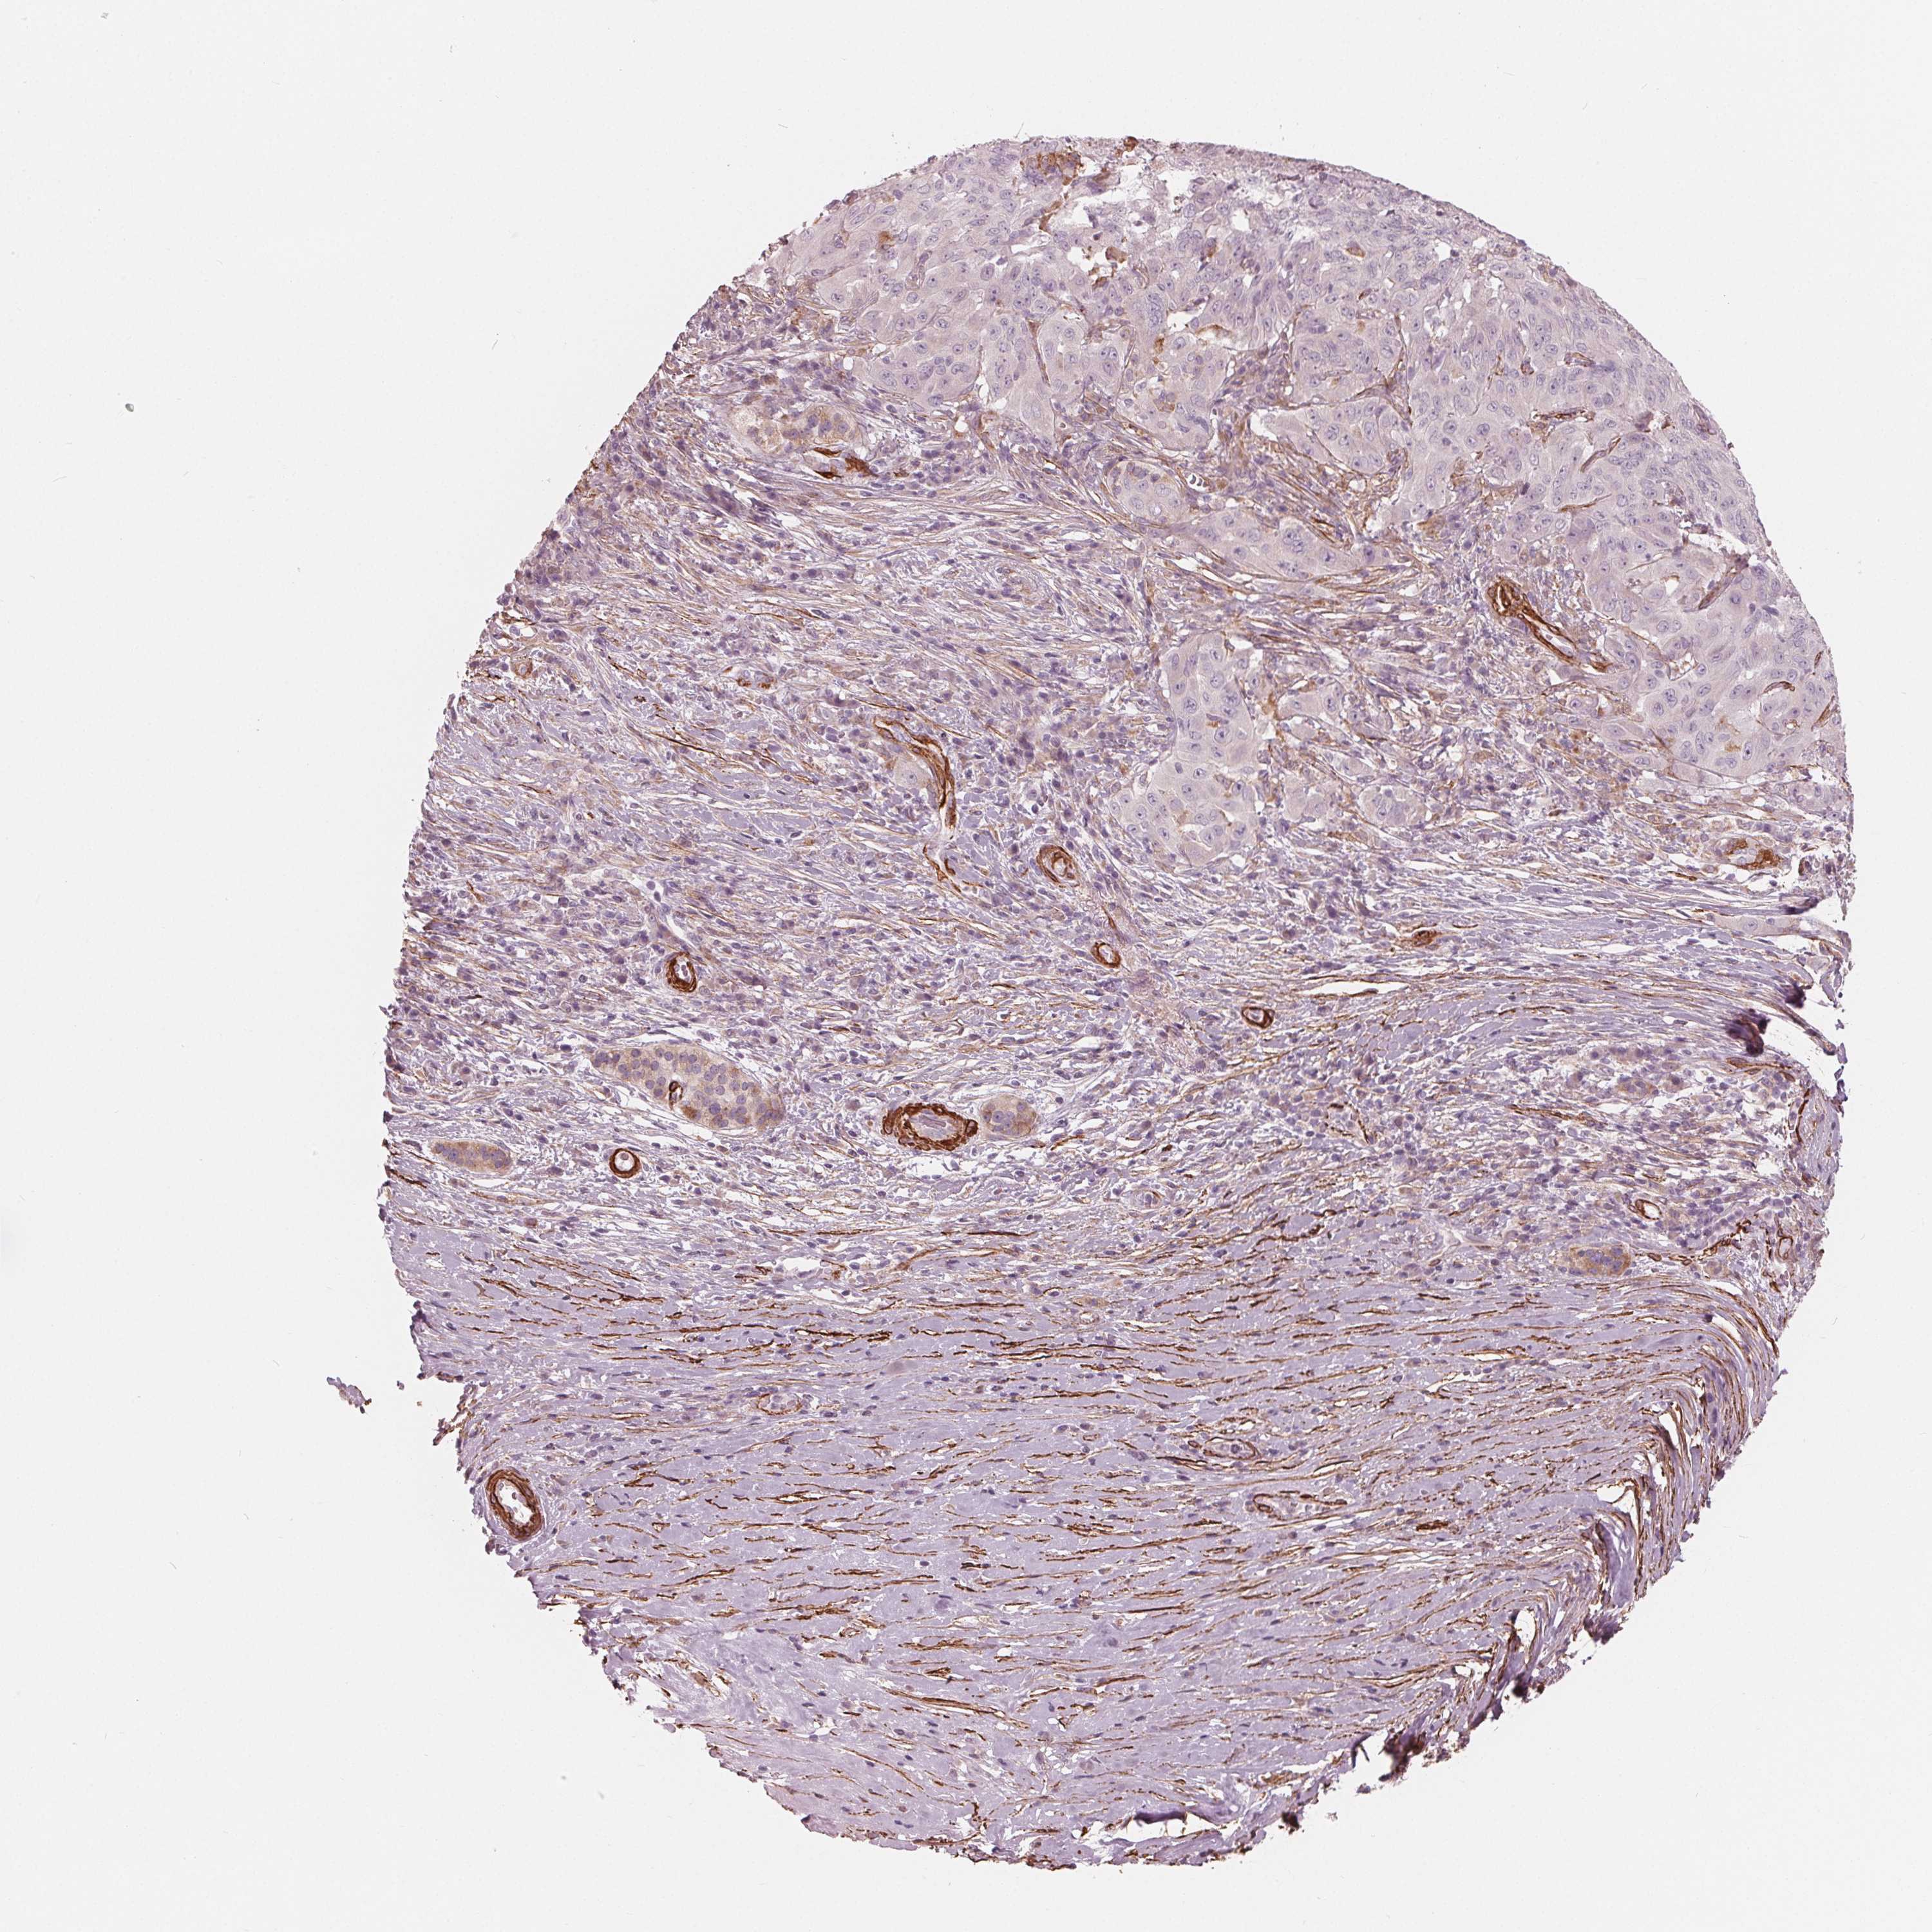

PANCREATIC CANCER - Protein expressioni

A mouse-over function shows sample information and annotation data. Click on an image to view it in a full screen mode. Samples can be filtered based on level of antibody staining by selecting one or several of the following categories: high, medium, low and not detected. The assay and annotation is described here.

Note that samples used for immunohistochemistry by the Human Protein Atlas do not correspond to samples in the TCGA dataset.

Antibody stainingi

Antibody staining in the annotated cell types in the current human tissue is reported as not detected, low, medium, or high, based on conventional immunohistochemistry profiling in selected tissues. This score is based on the combination of the staining intensity and fraction of stained cells.

Each image is clickable and will lead to virtual microscopy that enables deeper exploration of all samples and also displays staining intensity scores, fraction scores and subcellular localization as well as patient and tissue information for each sample.

Antibody HPA065946

Staining

High

Medium

Low

Not detected

Intensity

Strong

Moderate

Weak

Negative

Quantity

>75%

75%-25%

<25%

None

Location

Nuclear

Cytoplasmic/membranous

Cytoplasmic/membranous,nuclear

Adenocarcinoma, NOS